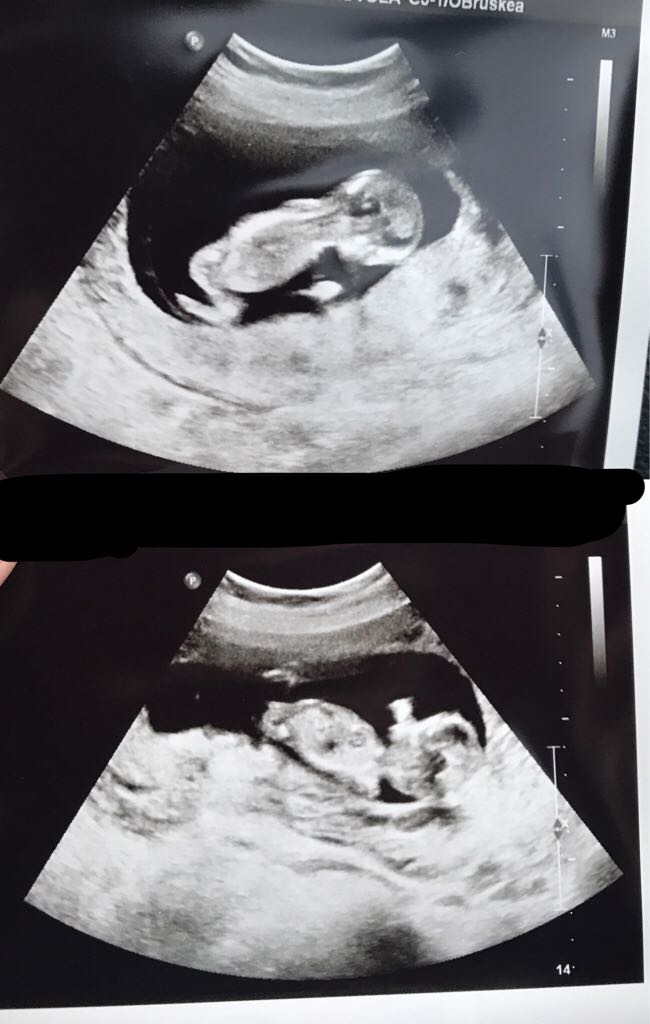

Meillä annettiin kolmannelle lupa tulla ja nyt odotellaan kaupantekijäisenä myös neljättä :) Huomenna vielä nt-ultra niin näkee onko molemmat vielä matkassa. Kauhuissaan tietty jaksamisen suhteen ku pojatkin on vielä pieniä ja tottakai taloudellinen puolikin mietityttää kovasti.. Mutta eiköhän kaikesta selviä ja nimenomaan kaksoset on kyllä etuoikeus :)